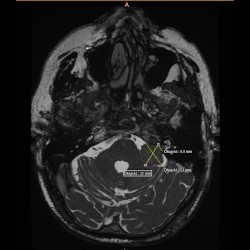

W dn. 15.09.2021 do Poradni Radioterapii zgłosił się chory z niedosłuchem lewostronnym i zaburzeniami równowagi. W wyniku MRI głowy w lewym kącie mostowo-móżdżkowym widoczna była lita masa silnie wzmacniającego się guza, który cienką wypustką wpuklał się do światła przewodu słuchowego wew.